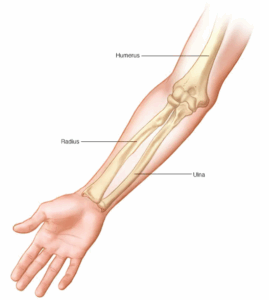

Arm fracture

A broken arm involves one or more of the three bones in your arm — the ulna, radius and humerus. One of the most common causes of a broken arm is falling onto an outstretched hand.